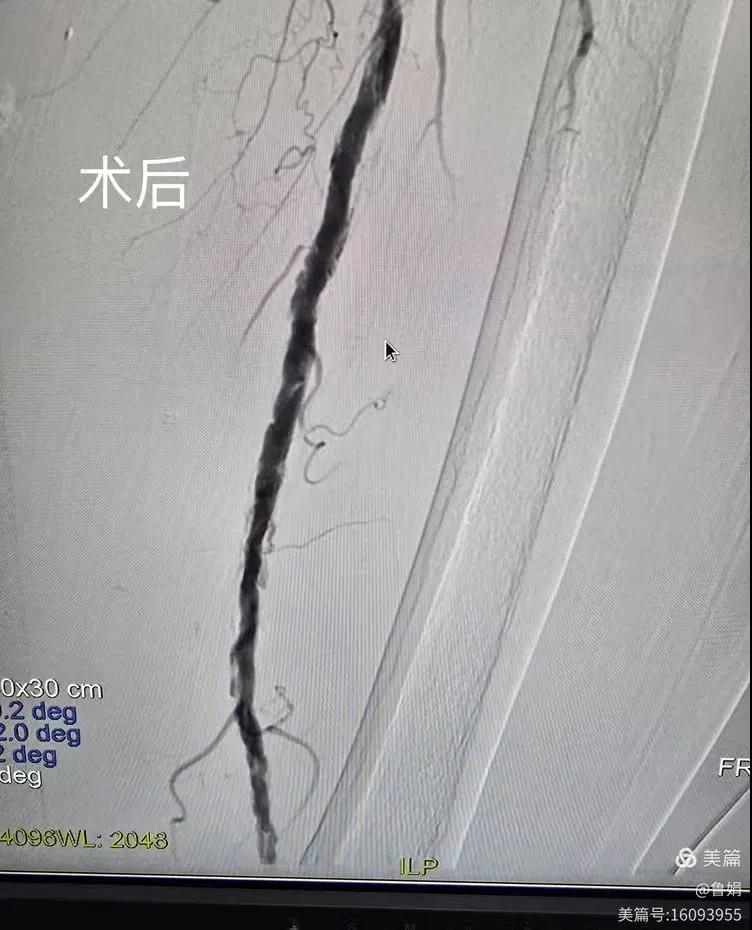

據(jù)悉,該患者,女,73歲,下肢動(dòng)脈硬化閉塞癥,“以靜息痛,間歇性跛行”入院,CTA評(píng)估:股淺動(dòng)脈,腘動(dòng)脈間斷性多段重度狹窄,外二科血管外科團(tuán)隊(duì)根據(jù)患者病情,結(jié)合檢查結(jié)果,經(jīng)過(guò)科室會(huì)診后,決定對(duì)該病人行介入治療。手術(shù)由周創(chuàng)業(yè)副主任與北大一院血管外科專家郭宏杰教授聯(lián)合開展,對(duì)股淺動(dòng)脈,腘動(dòng)脈重度閉塞段行血管開通+藥涂球囊擴(kuò)張成形,術(shù)后狹窄明顯緩解,血流恢復(fù)!

下肢動(dòng)脈閉塞的介入開通是外周介入領(lǐng)域難度最大的技術(shù)之一,這項(xiàng)微創(chuàng)介入手術(shù)的開展,實(shí)現(xiàn)了漯河市中醫(yī)院在下肢動(dòng)脈血管介入治療上零的突破,進(jìn)一步推動(dòng)了醫(yī)院介入治療技術(shù)的發(fā)展,讓患者足不出戶就能切實(shí)享受到優(yōu)質(zhì)的醫(yī)療資源,極大方便了患者就醫(yī)。(介入中心:魯娟)